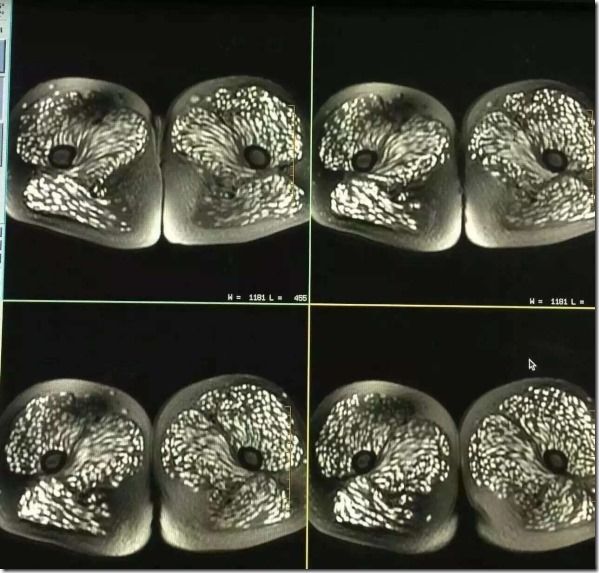

上は足のスキャンか